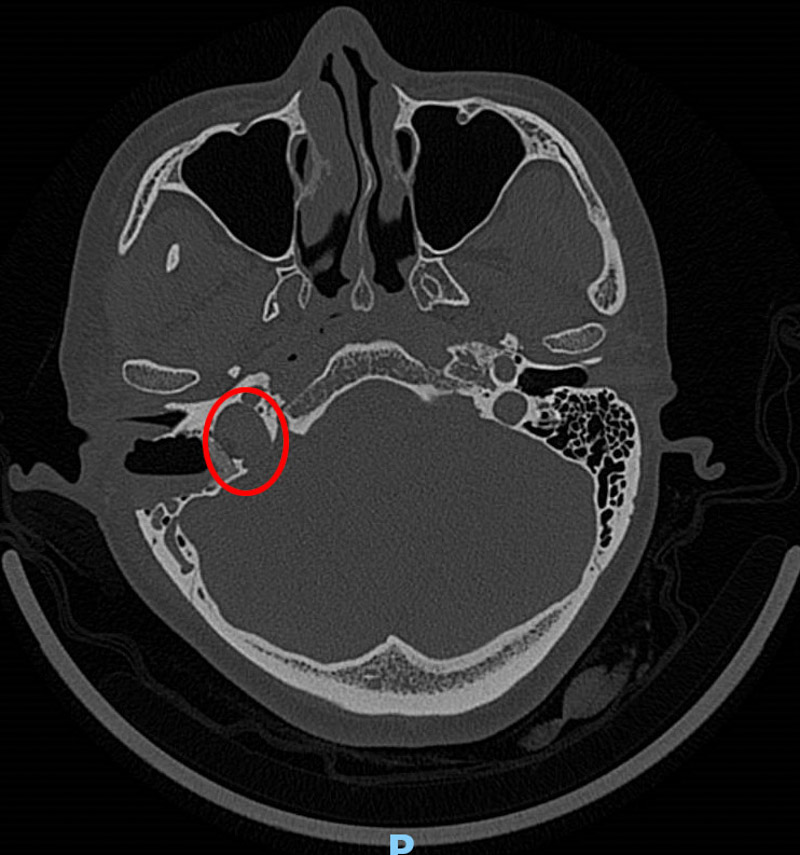

接診醫生了解情況后,為韋女士做了耳內鏡及聽力學檢查,并沒發現異常,但根據患者的實際情況并結合多年的經驗判斷,患者的右耳有可能患有血管搏動性耳鳴。為了進一步證實,患者進行了高分辨頭顱CT檢查,果不其然,放射科醫生在CT影像學中發現了蛛絲馬跡:患者的右側頸靜脈球高位,可疑合并前壁和外側壁缺損。這就是導致韋女士耳鳴的罪魁禍首!